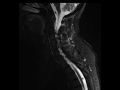

Interspinous Ligamentous Injury

58-year-old female status post fall. The STIR-weighted images demonstrate abnormal hyperintense signal between the spinous process of C4, C5, and C6. There is abnormal soft tissue stranding compatible with edema at these sites on the sagittal T2 and T1-weighted images. The findings are compatible with an interspinous ligamentous injury given the reported history of trauma. Incidental note is made of prevertebral soft tissue edema from the C4 to C6 vertebral levels compatible with ligamentous injury to the anterior longitudinal ligament. Hyperflexion sprain injuries result from injuries to the soft tissues without fracture.